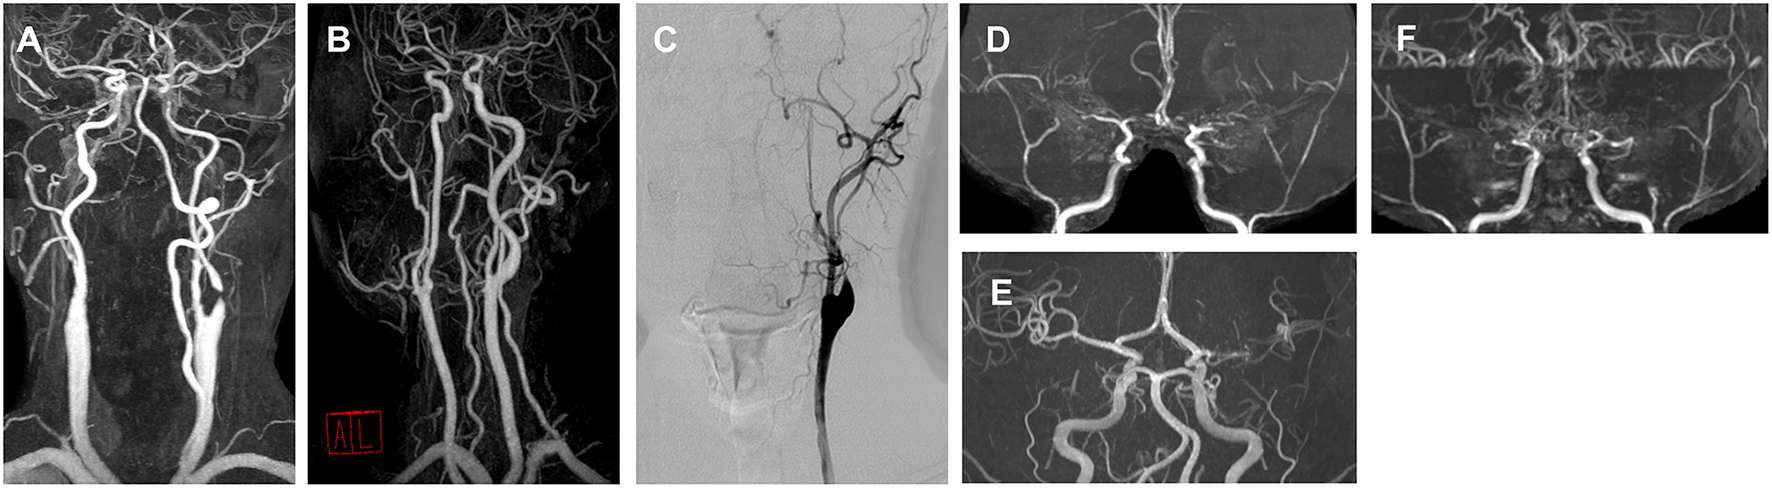

The vascular status of representative cases for each movement phenotype is presented in Figure 3, and their clinical characteristics are shown in Supplementary Table 3.

Figure 3

Angiography of representative cases for each movement disorder phenotype. (A) A 76-year-old male with right hemichorea and contralateral proximal internal carotid artery (ICA) stenosis. (B) A 57-year-old male with limb-shaking of the left arm and contralateral proximal ICA stenosis. (C) A 56-year-old male with a myoclonus of the right arm and leg and contralateral proximal ICA stenosis. (D) A 24-year-old male with left arm dystonia and moyamoya disease. (E) A 46-year-old female with right hemiparkinsonism and contralateral middle cerebral artery (MCA) stenosis. (F) A 28-year-old female with a mixed phenotype (left hemichorea and hemidystonia) and moyamoya disease.